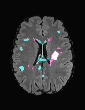

In recent years, data-driven machine learning (ML) methods have revolutionized the computer vision community by providing novel efficient solutions to many unsolved (medical) image analysis problems. However, due to the increasing privacy concerns and data fragmentation on many different sites, existing medical data are not fully utilized, thus limiting the potential of ML. Federated learning (FL) enables multiple parties to collaboratively train a ML model without exchanging local data. However, data heterogeneity (non-IID) among the distributed clients is yet a challenge. To this end, we propose a novel federated method, denoted Federated Disentanglement (FedDis), to disentangle the parameter space into shape and appearance, and only share the shape parameter with the clients. FedDis is based on the assumption that the anatomical structure in brain MRI images is similar across multiple institutions, and sharing the shape knowledge would be beneficial in anomaly detection. In this paper, we leverage healthy brain scans of 623 subjects from multiple sites with real data (OASIS, ADNI) in a privacy-preserving fashion to learn a model of normal anatomy, that allows to segment abnormal structures. We demonstrate a superior performance of FedDis on real pathological databases containing 109 subjects; two publicly available MS Lesions (MSLUB, MSISBI), and an in-house database with MS and Glioblastoma (MSI and GBI). FedDis achieved an average dice performance of 0.38, outperforming the state-of-the-art (SOTA) auto-encoder by 42% and the SOTA federated method by 11%. Further, we illustrate that FedDis learns a shape embedding that is orthogonal to the appearance and consistent under different intensity augmentations.